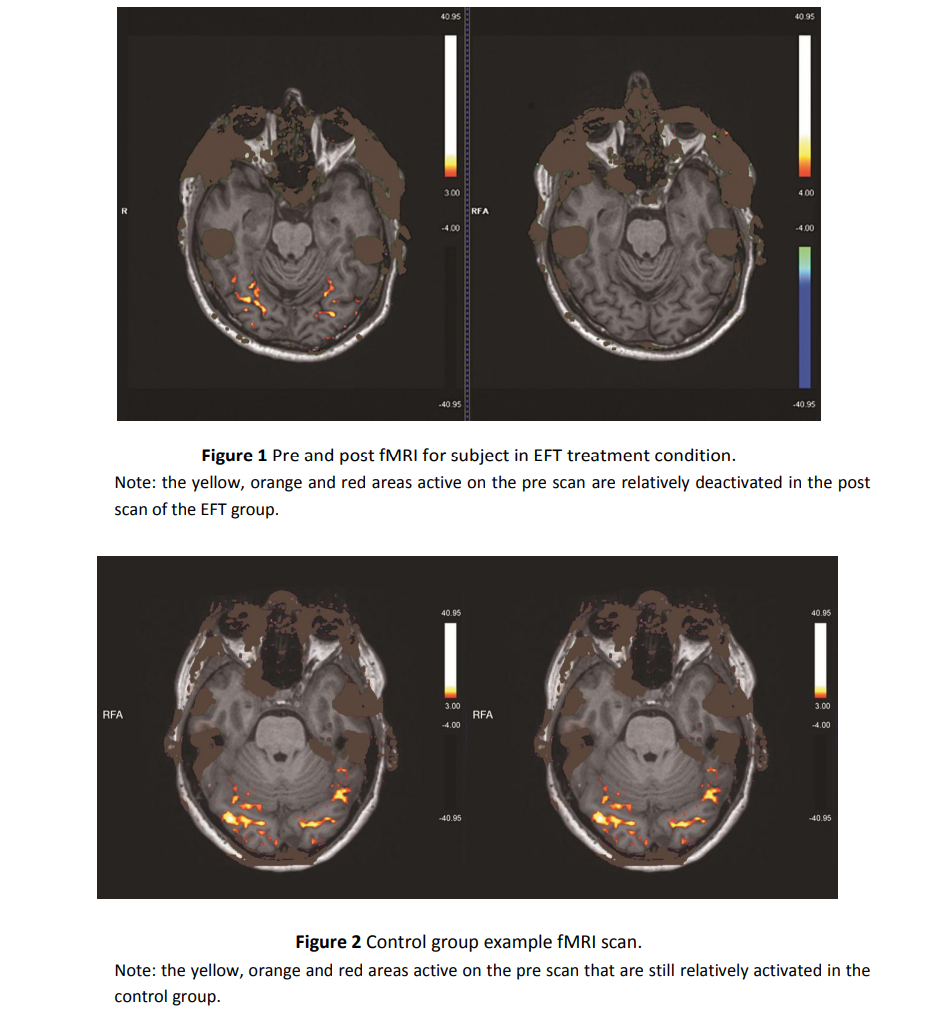

EFT 기법을 적용하며 뇌 영상 검사를 하는 연구가 있었습니다. 이 연구에서 EFT는 표적이 되는 감정을 담당하는 뇌 영역을 직접 변화시키는 것으로 나타났습니다.

아래 실험은 비만환자의 이상 식욕을 줄이기 위해 감정자유기법을 적용한 케이스입니다. (참고 An Initial Investigation of Neural Changes in Overweight Adults with Food Cravings after Emotional Freedom Techniques //  doi:10.21926/obm.icm.1901010)

아래 사진을 보시면 뇌에서 식욕을 담당하는 부분의 활성도가 떨어짐을 관찰할 수 있습니다. 그 아래 대조군의 경우 활성도가 그대로입니다. 가짜로 시행한다고 해서 뇌가 반응하지 않는 다는 뜻이죠. 단순 플라시보가 아니라는 뜻입니다.

즉, 단순한 심리 효과가 아니라 신경학적으로 실제 작용하는 치료법이라는 거죠!